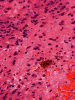

Pathology of the Case: MRI shows a large mass with the more solid component located in the lateral ventricles and the cystic component protruding into the cortical area. The solid area is enhanced (Panel A). On low magnification, the lesion has alternating area of high and low cellularity (Panel B) with scattered calcifications in some of the sections. Medium and high magnification demonstrates perivascular coronary arrangement of cytoplasmic processes (Panel C, D, and E). The nuclei are bland and mitotic figures are not readily seen. Randomly scattered brown pigment containing cells are found in multiple areas of the tumor (Panel F, G, and H). Scant lipidized cells with enlarged nuclei (Panel I) are also present. The tumor cells are strongly positive for glial fibrillary acidic protein (GFAP) (Panel J and K) and S100 protein but are negative for epithelial membrane antigen (EMA), neurofilament proteins, and NeuN. The overall Ki67 labeling is low but focal small areas (about the size of one high power field) has increased labeling. The pigment appears to be melanin on microscopic examination. These pigments are positive with Fontana-Masson stain (Panel L) but negative for Prussian blue stain for iron (Panel M). These features confirmed that these are melanin pigments. The pigment granules are positive for periodic acid-Schiff reaction (N), negative for Ziehl-Neelsen (acid fast) stain..